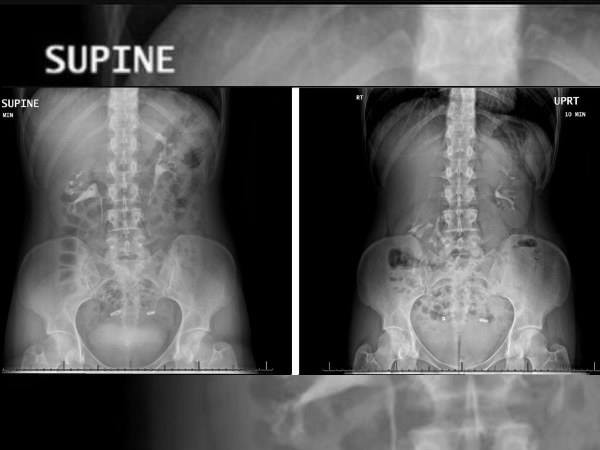

Phim chụp X-quang cho thấy quả thận chạm vào xương chậu mỗi khi cô gái đứng lên (Ảnh: Boldsky)

Hội chứng này thường xuất hiện ở những người có hình thể gầy gò. Trong trường hợp của người phụ nữ 28 tuổi này, mỗi khi cô đứng lên, vị trí của thận dịch chuyển tới 6 cm, va đập vào hai đốt sống lưng và xương chậu. Đây là lý do chính khiến cô bị đau liên tục.